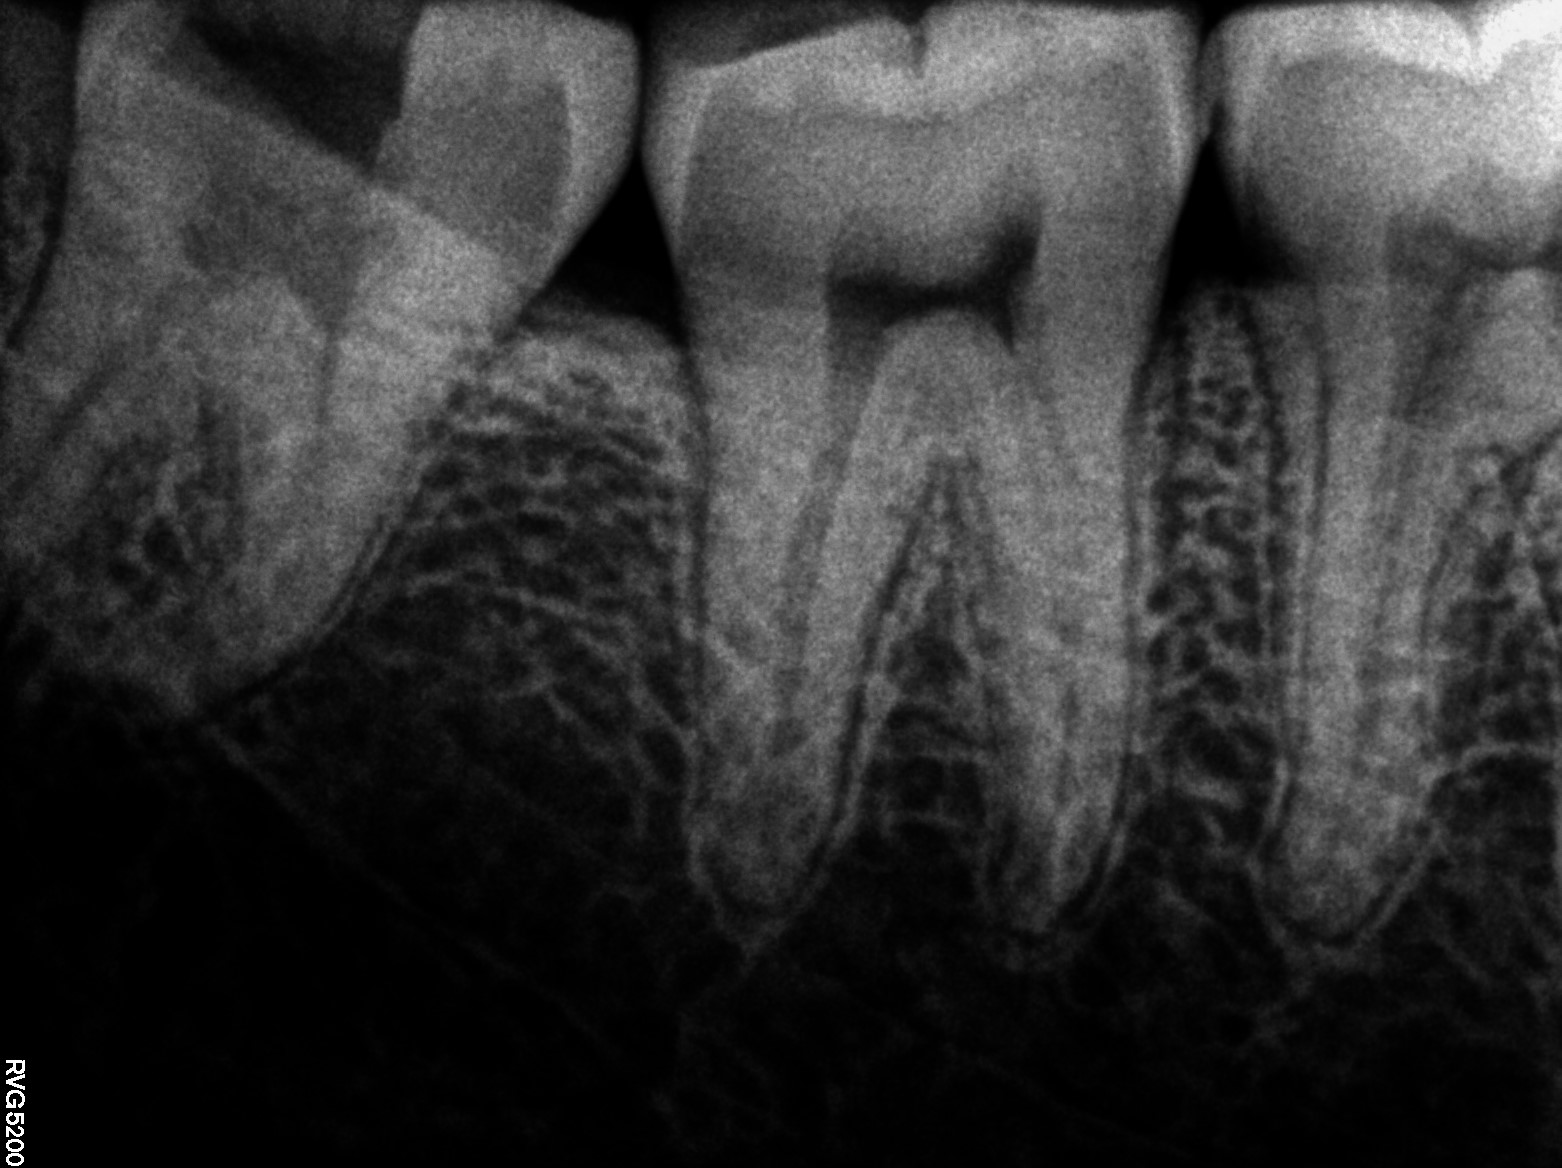

Dental Radiographs FHIR: DocumentReference · LOINC 24641-7

R65.jpg

24641-7